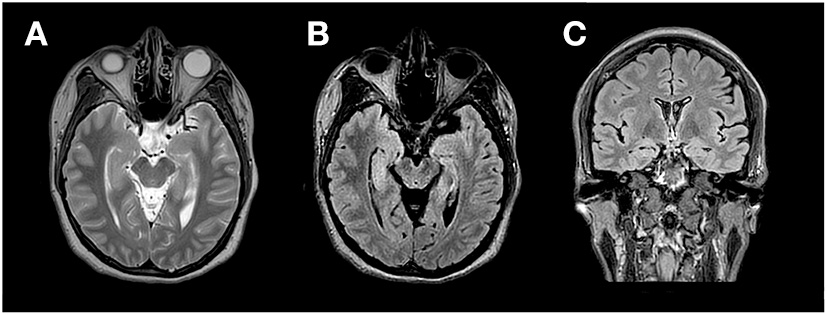

After her third seizure, the patient was hospitalized for further examination and treatment. She was prescribed oral levetiracetam (1.0 g/day) to control seizures. Neurological examination was normal except for short-term memory impairment. Further assessment of the patient's overall cognitive and memory functions revealed a score of 24/30 (normal range 26–30) on the Montreal Cognitive Assessment (MoCA), showing impaired orientation, attention, and short-term memory. Results of the Auditory Vocabulary Learning Test showed a score of 6 for immediate recall, 9 for delayed recall, and 13 for recognition, indicating impaired memory function. Laboratory tests showed that blood cell count, blood biochemistry, thyroid function, rheumatic disease screening were within the normal range. Tumor marker detection revealed an elevated CA125 level (34.79 U/mL, normal range 0–30.2 U/mL), while the levels of other tumor markers were normal. Semi-quantitative detection of paraneoplastic neuron antibody showed that the GAD65 antibody was positive, with a titer of 32 AU; other antibodies were negative. Thoraco-abdomino-pelvic computed tomography showed a few foci of fibrosis in the middle lobe of the right lung and ovarian cysts on the left side, without other abnormal findings. Pelvic ultrasound and further examination of the bilateral adnexal showed no abnormalities. Subsequently, the findings of pelvic computed tomography were considered a menstrual-related ovarian cyst, and teratoma was excluded. Ultrasound of the thyroid, breast, bilateral neck, and axillary lymph nodes showed a benign right breast nodule and a left thyroid cyst, with no change in size or morphology compared with that of the patient's physical examination conducted 2 years ago. Magnetic resonance imaging of the brain showed abnormal signals in both medial temporal lobes, predominantly on the right side (Figure 1). Video electroencephalogram monitoring revealed widespread diffuse slow waves during wakefulness.

Figure 1

MRI (3.0T) at the time of presentation. Axial T2 Weighted Image (A), Axial Fluid attenuated inversion recovery (FLAIR) sequence (B) and coronal FLAIR (C) show cortical thickening and hyper intense signal in the medial aspect of bilateral temporal lobes Right > Left.